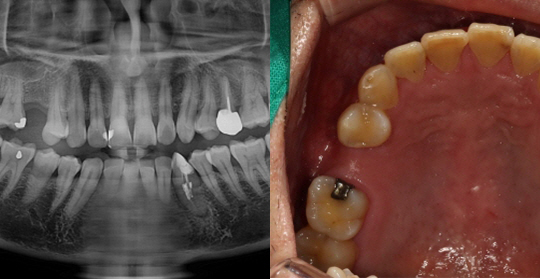

(38세 남 환자)